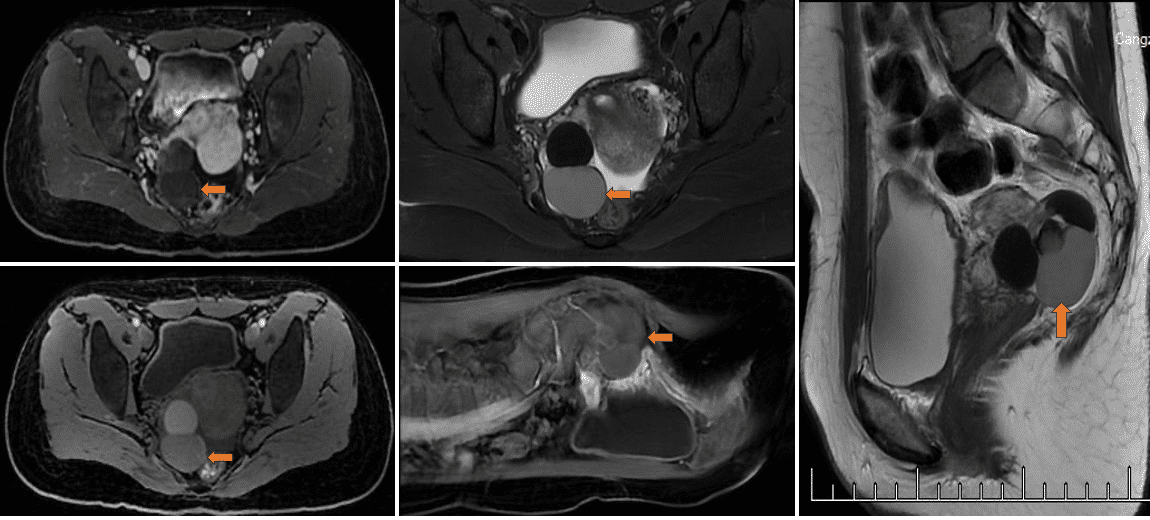

腹腔CT平扫可见子宫右侧可见团块状混杂密度影,其内可见多发类圆形高密度影聚集,病灶范围约为5.4×3.5cm。阑尾增粗,其内可见高密度影。建议完善MR强化检查。

腹腔MR增强:右侧附件区见多发大小不等稍短T1长、短T2信号影,边界清晰,增强扫描分隔样强化,最大截面大小约为3.2cm×4.9cm。子宫前壁凹陷,子宫前壁结合带增厚,左侧附件区形态及信号可。子宫内膜未见明显增厚,膀胱充盈可,壁不厚。双侧髂血管内侧见条状软组织影,增强扫描同静脉强化方式基本一致。盆腔内见液体信号影。右侧附件区占位,考虑为巧克力囊肿。